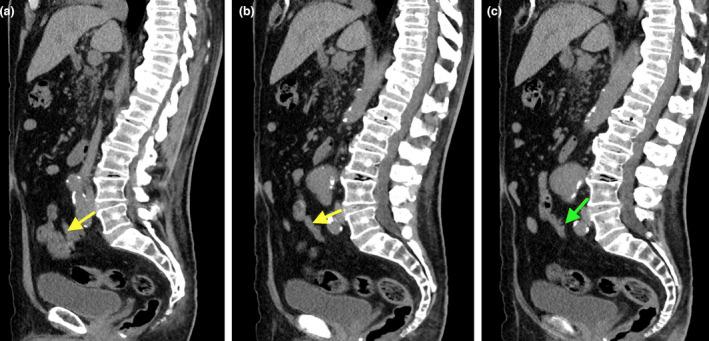

Complicated appendicular diverticulitis.

Appendiceal diverticulitis, a frequently underdiagnosed entity, differs from typical appendicitis by the presence of an inflamed appendiceal diverticulum. Appendiceal diverticulitis is a surgical emergency which has an increased risk of perforation compared to typical appendicitis. We will discuss a surgically and pathologically confirmed case of complicated appendiceal diverticulitis and its management implications.